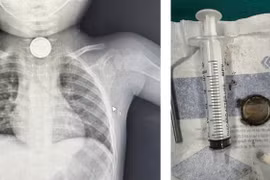

Pin sử dụng cho các loại đồ chơi trẻ em chủ yếu là loại pin có hình dạng tròn dẹt có kích từ 10-20mm. Với kích thước như vậy trẻ khi cầm chơi viên pin cũng rất dễ dàng nuốt và viên pin có thể mắc lại tại thực quản.